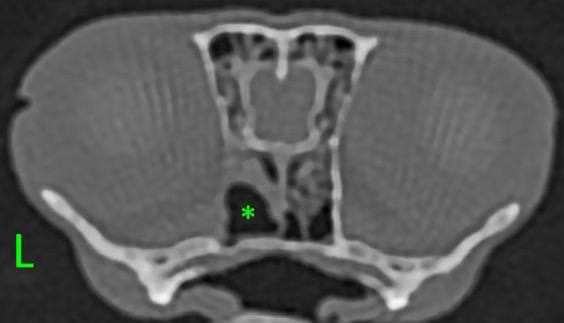

Маленький фенёк по кличке Груня в июне 2025 поступил в нашу клинику с диагнозом злокачественной опухоли полости носа и носоглотки (по данным КТ больше оснований думать об аденокарциноме). Хирургическое лечение таких опухолей практически невозможно даже у крупных собак, тем более у животного размером чуть больше кошки; лечащий врач-экзотолог, Алексей Анатольевич Первов, направил пациента для проведения лучевой терапии.

Курс облучения прошёл без осложнений, а при выполнении контрольного КТ головы от августа 2025 врач-рентгенолог Евгений Леонидович Кемельман подтвердил полную регрессию опухоли. Сейчас пациент чувствует себя отлично и живёт полноценной жизнью.